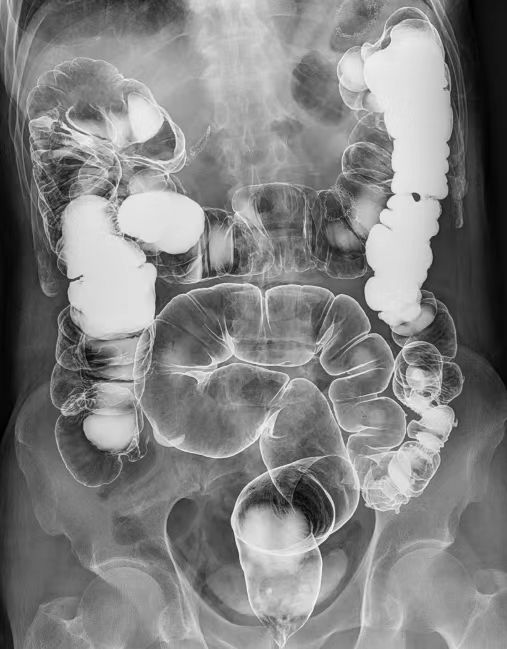

(三)下消化道造影

用于直肠、结肠及回盲部病变的造影诊断(气钡剂双重造影)。